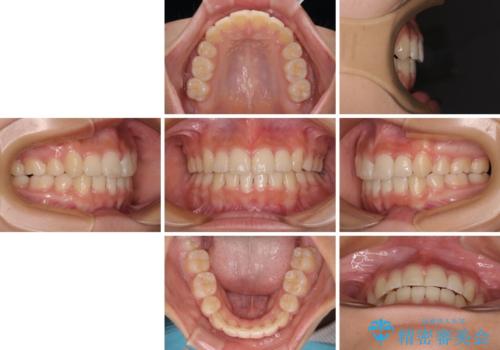

上顎骨幅が狭い 急速拡大装置を併用した抜歯矯正

- 歯列全体の叢生を気にして来院された患者様です。

検査を行った結果、上顎骨の横幅が相対的に狭いことが分かり、叢生が強いことから、急速拡大装置にて上顎骨を側方に拡大することで、叢生の解消と奥歯の咬み合わせ改善を図ることとしました。

一般的には上下左右の第一小臼歯4本を抜歯する必要がありますが、拡大量によっては非抜歯矯正の適用となる可能性があるため、まずは非抜歯矯正で治療を開始し、抜歯が必要と判断された時点で速やかに4本抜歯を行うこととしました。

急速拡大後、歯列はきれいに並んだのですが、口元が出っ歯になってしまったため、速やかに抜歯を行い、治療期間がいたずらに遅延することのないようにしました。